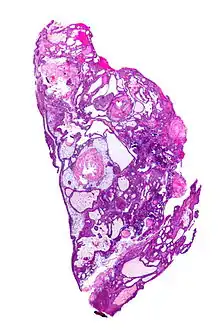

| Very low magnification micrograph of an adamantinomatous craniopharyngioma. HPS stain. | |

On macroscopic examination, craniopharyngiomas are cystic or partially cystic with solid areas. On light microscopy, the cysts are seen to be lined by stratified squamous epithelium. Keratin pearls may also be seen. The cysts are usually filled with a yellow, viscous fluid rich in cholesterol crystals. Of a long list of possible symptoms, the most common presentations include headaches, growth failure, and bitemporal hemianopsia.

Micrograph showing the characteristic features of an adamantinomatous craniopharyngioma - cystic spaces, calcifications, and "wet" keratin, HPS stain

Micrograph showing a papillary craniopharyngioma, HPS stain